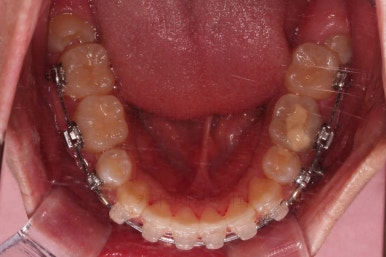

가지런하게 하는 단계를 거친 뒤,당기기 과정에 들어가는데요.

이 과정에서 입이 들어가는 양, 중앙선, 기울기, 앞니 각도 등등 많은 것을 신경써서 당기기를 해주는데요.

이 때 필요한 것이 미니스크류 입니다.

예전과는 다르게 미니스크류를 이용해서 좀 더 정교하고 고난이도의 치료가 가능해지게 된거죠.

다양한 위치/방향/방법으로 치열을 개선해 나갑니다.

환자부니 원하시는 포인트, 디테일을 정리하면서 마무리를 해줍니다.